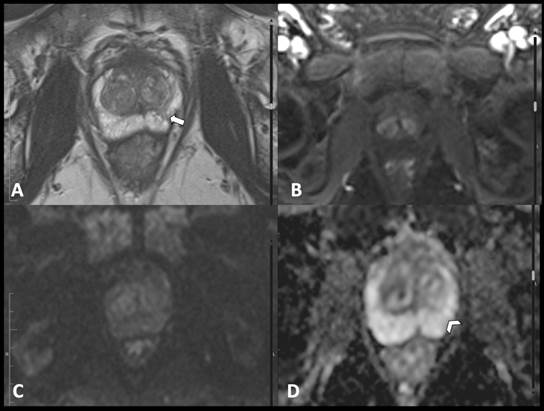

observador 3). Estos revisaron los estudios que cumplieron los criterios de inclusión (paciente con sospecha de carcinoma de próstata y RM con adecuados parámetros para su evaluación) mediante un visor de imágenes médicas (Hiruko, IMEXHS, Bogotá, Colombia). Calificaron las imágenes con los criterios principales del PI-RADS v. 2.1, consignaron los resultados en la herramienta de recolección descrita y emitieron una clasificación final para cada caso. En las Figs. 2, 3, 4, 5 y 6 se muestran ejemplos de las imágenes obtenidas y evaluadas según la clasificación PI-RADS v. 2.1.